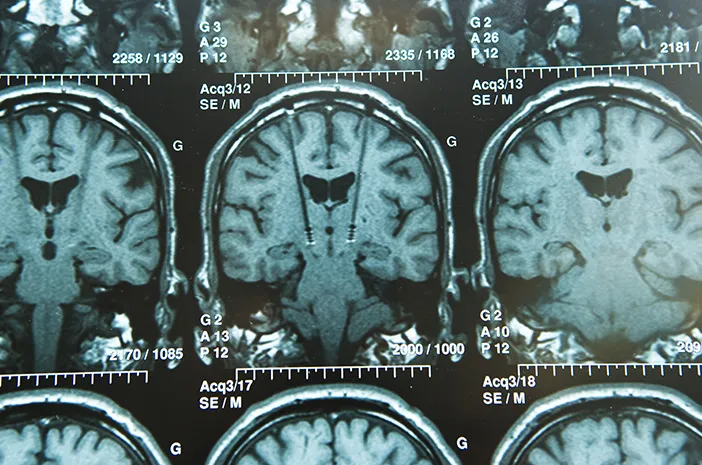

- Penentuan lokasi otak: Dokter menggunakan MRI atau CT scan untuk menentukan titik tepat di otak yang akan ditanam elektroda, biasanya di nukleus subtalamikus atau globus pallidus internus.

- Pemasangan elektroda: Melalui pembedahan kecil di tengkorak, elektroda ditanam ke bagian otak target. Proses ini biasanya dilakukan dalam keadaan sadar agar dokter bisa mengamati reaksi pasien.